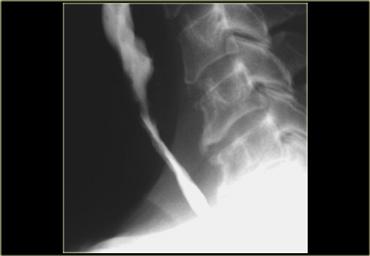

Gai xương (mũi tên) có thể chèn ép vào thực quản và hạ họng.

Tuy nhiên, chúng hiếm khi gây ra triệu chứng lâm sàng.

Trong trường hợp hình bên trái, nang đẩy hạ họng và thực quản đã cản quang (mũi tên) ra phía sau, đồng thời đẩy khí quản và thanh quản (dấu hoa thị) ra phía trước.